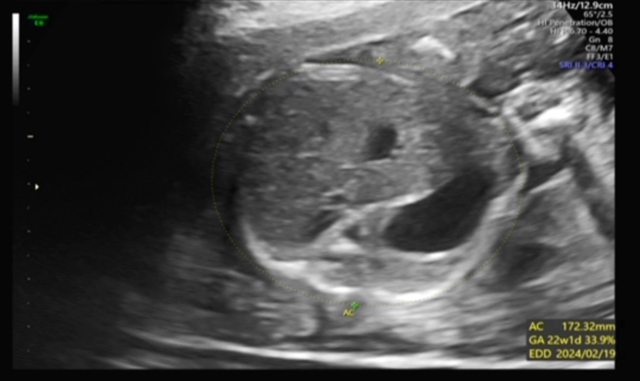

昨天去產檢,醫生覺得寶寶的胃偏大之後要注意觀察 我搜尋了一下好像只有看到胃太小的文,請問大家有沒有遇過類似情況? 我後來看了一下22週的高層次照片,那時候寶寶也是胃大大的,但那時只說是寶寶可能剛 吃飽 https://i.imgur.com/amlKp09.jpg

每一胎的狀況真的不一樣,這次第二胎先歷經羊水少週數小三週,到現在追到剩小一週, 但昨天醫生又提醒胃好像偏大,只希望二寶可以健康平安出生~ -- ※ 發信站: 批踢踢實業坊(www.ptt.org.tw), 來自: 101.12.24.40 (臺灣) ※ 文章網址: https://www.ptt.org.tw/BabyMother/M.1700797726.A.8D2